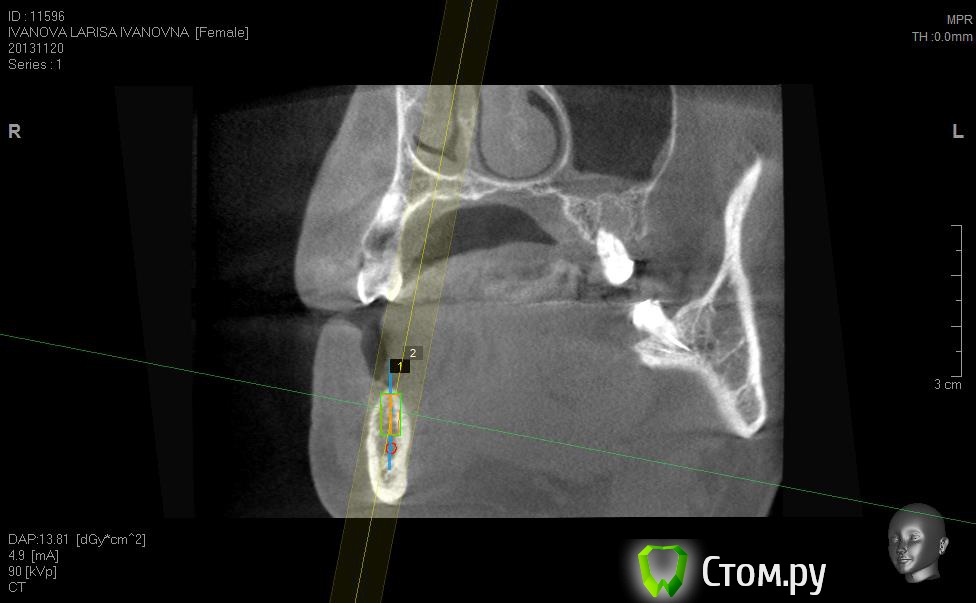

Neilrus Опубликовано 2 марта, 2014 Поделиться Опубликовано 2 марта, 2014 (изменено) Здравствуйте, коллеги, уделите 6 минут новичку…у меня тут проблема, она абсолютно не проблема для того, кто хоть пару раз делал расщепление гребня,а я вот только курсы закончил и у меня планируется через 7 дней операция. Вроде все понял, но пока стремаюсь.Посморите снимки, пожалуйста, а я напишу тот протокол, который хочу применить, как на курсах понял, поправьте, если что не так )) Спросил бы у лектора, но ведь так всегда, да?)Планирую иплантаты по месту 45,46 зубов.Гребень узкий в обл 45 з и близко нч нерв, как раз поднимается к ментальному отвертстию. С этим и связан страх. Никаких транспозиций делать пока не готов. В арсенале нет пьезотома пока, вот пару таких операций сделаю и куплю.Планирую поставить 4,2*8 для 45 зуба и 4,2*11,5 для 46 зуба (Мis Seven) . Соединю коронки, т.к. премоляр коротковат. Итак, план по захвату таков:1)Разрез чуть язычнее середины гребня, откидываем слиз-надк лоскут с аккуратностью в области менталиса.2)По центру гребня делаем горизонтальный распил сепарационным диском диаметром 7 не доходя до зубов по 3 мм. Глубина распила получается 3,3. Потом беру диск 10 и глубина уже 4,8.3)Мелким 7мм диском делаю дистально вертикальный распил на глубину 3,3 длиной с длину имплантата моляра 11,5, а медиально тем же диском на длину 4-5 мм, ниже страшно, боюсь нерв задеть. На верхушке гребня соединяем распилы (черные линии на моем рисунке). Делаем бором твердосплавным шаром компактостеотомию в преполагаемом месте перелома.4)Берем долото и вставляем в горизонтальный разрез и постукиваниями молоточка продвигаем его на глубину до 8мм по всей длине разреза (длина миниального импланта). Чуть покачивая из стороны в сторону, при этом убирая закругления от диска внутри горизонтального распила. (На рисунке, который сам нарисовал – это красная зона).5)Немного раздвинув края в месте предполагаемых имплантатов пилотом 2мм прохожу на глубину имплантатов. Проверяем параллельность.6)Загоняю по очереди мисовские компрессионные винты на глубину имплантатов до диаметра третьего винта 2,4- 3,7 (т.к. импланты 4,2)7)Теперь они вроде как должны быть нормально раздвинуты ( здесь я не понял, нужно проходить фрезами из хир набора или так хорошо войдут) Может финишной фрезой пройти хотя бы на всю глубину имплантатов? Подскажите, пожалуйста.8)Дальше заполняю пустоты MP3, фиксирую пинами MCT 2.75 мембрану evolution толстую на 2 мм ниже коспактостеотомии, перекидываю на язычную сторону под надкостницу краешек запихиваю.9)Мобилизую лоскут, ушиваю все наглухо и надеюсь на лучшее. ВОПРОСЫ:1)не коротковат ли имплант 4,2*8, но ведь я соединю их? Можно немного наклонить его медиально, выход шахты оставить там же, но апикальную часть ближе к моляру, тогда длина 10 выйдет, но там и так не получается соостно с зубами имплант размстить, а тут его и такая ангуляция, не хорошо, я думаю.2)Отслойка лоскута медиально- правильно я написал или порвется тогда и лучше рассечь связку на 44 и медиально вниз.3)Фрезы хирургические нужно использовать при нормальном раздвигании краев гребня? Кстати, нормально-это сколько для диаметра имплантата 4,24)Язычно нужно как-то дополнительно фиксировать мембрану?5)MP3 мешать с аутокостью и кровью из ловушки?6)Как лоскут мобилизовать медиально рядом с ментальным нервом? Пластика зкпд будет одновременно с открытием.Спасибо вам за ваше время ) Изменено 8 мая, 2014 пользователем Bier Ссылка на комментарий